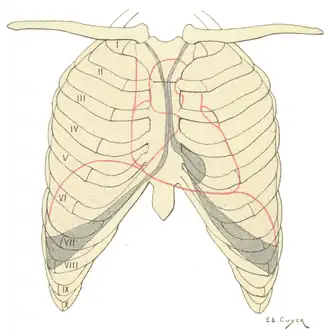

Protecție pe cutia toracică a inimii, plămânilor și diafragmei. Zonele umbrite indică întinderea cavităților pleurale care nu au umplut plămânii. | |

Cutia toracică (în latină thorax), sau coșul pieptului, este o parte din schelet formată din coaste, stern și o parte din coloana vertebrală. Cavitatea interioară formată de thorax se numește în latină Cavum thoracis. În cavitatea toracică se află ca organe principale inima și pulmonul (plămânul). Cavitatea toracică este separată de cavitatea abdominală prin diafragmă, care este mușchiul respirator principal.